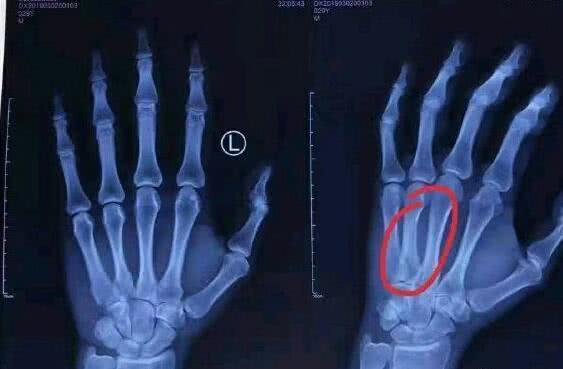

辽宁队很快做出回应,表示已经为韩德君联系好了专家,大韩会到北京进行治疗。有网友随后曝光了一张韩德君手部受伤处X光的照片,并透露他在北京积水潭医院完成了石膏外的固定,大韩将采取保守治疗,恢复时间预计是六周。